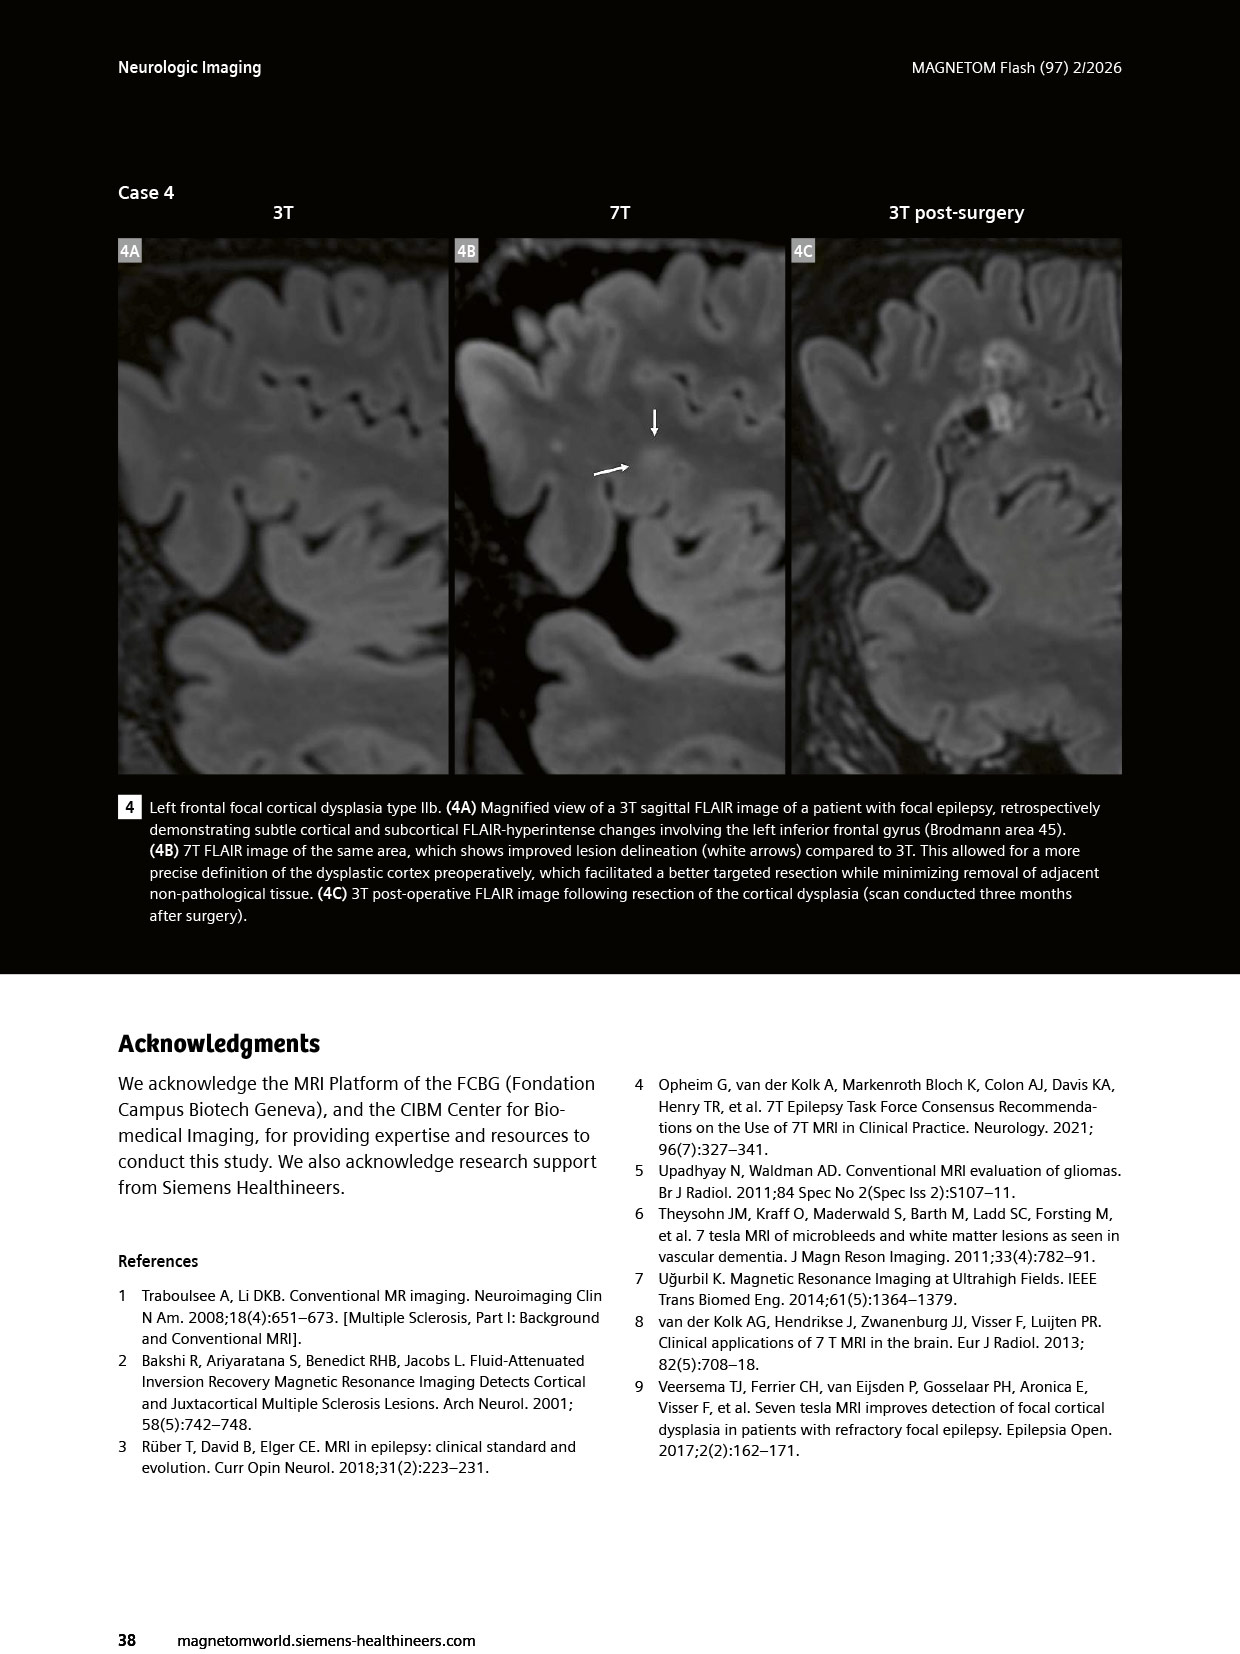

The article ” “Clinical Value of Optimized FLAIR Imaging at 7 Tesla: Neuroimaging Case Examples.” has been featured in MAGNETOM Flash, Issue 97 (2/2026, ISMRM Edition). Co-authored by Emilie Sleight, CIBM MRI EPFL Section and Fréderic Grouiller, CIBM MRI HUG UNIGE Section, Felix Kurtz, HUG, presents our continued commitment to advancing ultra-high-field MRI and its clinical translation.

The article highlights how optimised 7T FLAIR imaging enhances lesion detection and characterisation, with compelling clinical cases demonstrating its added value in neurological disorders such as multiple sclerosis and epilepsy. This work further underscores the growing role of 7T MRI in bridging cutting-edge research and clinical practice.